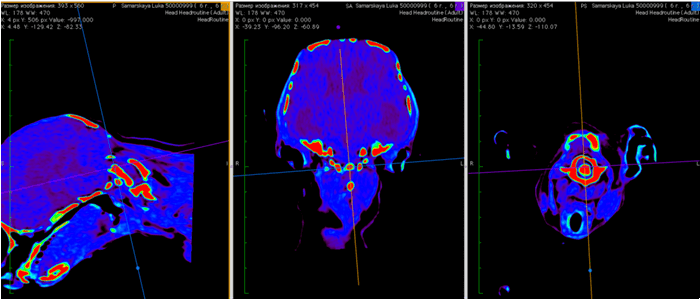

А. МРТ во фронтальной плоскости. Б. рисунок.

МРТ исследование пациентов с атланто-аксиальной сублюксацией

МРТ обеспечивает превосходное разрешение при исследовании нервной паренхимы и позволяет выявить другие патологии мозга, такие как дорсальную компрессию С1-С2, атланто-окципитальный оверлепинг, Киари и прочее.